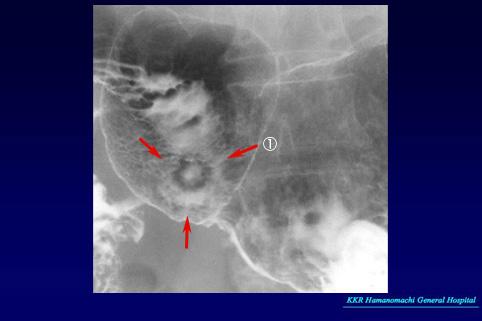

Criteria of Hist.ClassificationMalignant epithelial tumor/Others

LocationStomach/Antrum

Technique, MethodX-ray

Macroscopic TypesType 0/IIa (IIa+IIc) Superficial elevated and depressed type

Size15 - 19

Depth of Tumor Invasionsubmucosa